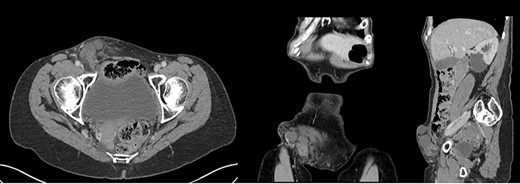

She proceeded to computed tomography (CT) of her chest, abdomen and pelvis, which demonstrated acute appendicitis within a right, direct inguinal hernia (Amyand’s hernia) with no features of perforation, bowel obstruction or collections (Fig. 1).

CT scan images of a 68-year-old woman who presented with acutely inflamed appendix within a right inguinal hernia sac (Amyand’s hernia) during COVID-10 pandemic.